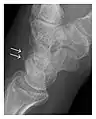

Figure 6: Subtle anterior talar fracture in a 39-year-old man presenting with ankle pain after a fall. (a) Anteroposterior radiograph shows a subtle oblique radiolucent line through the talus (white arrows). (b) Sagittal CT reformation confirms the presence of an anterior talar fracture with cortical offset (black arrow). Avulsion fractures, which consist of a detached bone fragment resulting from a ligament or tendon pulling away from the bone, may also present with subtle radiographic signs. Tiny osseous fragments near the presumed attachment site of a ligament suggest this diagnosis. Common sites are the lateral tibial plateau (the Segond fracture), the spinal tuberosity of the tibia resulting from anterior cruciate ligament avulsion, and the ischial tuberosity.[1]